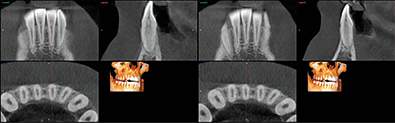

CBCT analysis revealed limited alveolar boundaries on the buccal and lingual of the mandibular anterior teeth (Fig. 3).

Fig. 3 Fig. 4

The location of the roots of the maxillary right dentition closely proximate the buccal and palatal cortical plates of the alveolar processes, which were thin particularly at the canine and first premolar with thicker cortex regions lateral to the second premolar and first molar (Figs. 4-7).